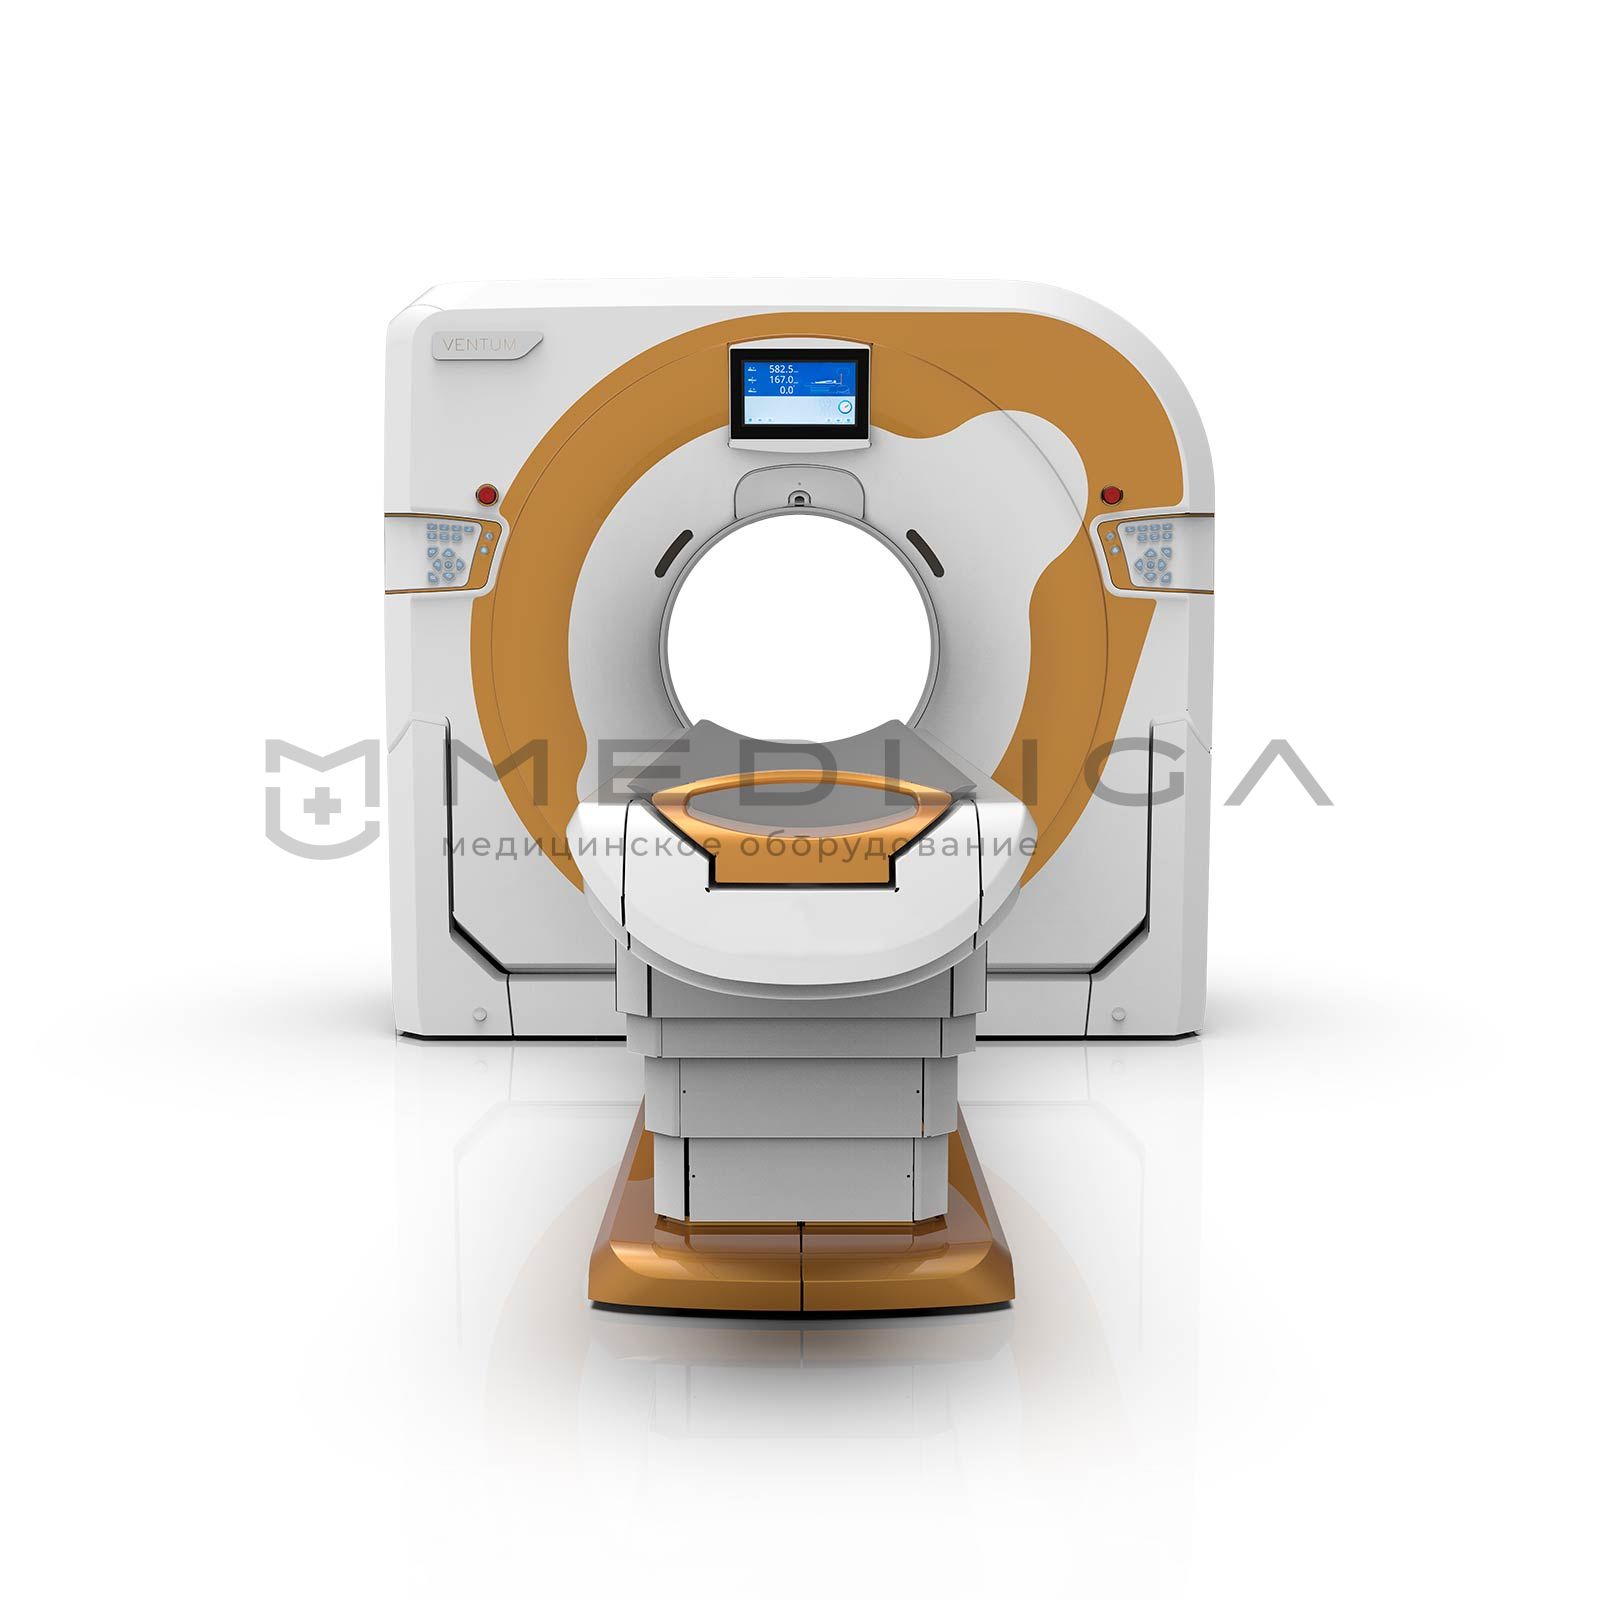

Компьютерный томограф ADVIN Ventum Pro 128/128S

В настоящее время рентгеновские компьютерные томографы (КТ) используются во многих больницах, поликлиниках и частных медицинских центрах для быстрого и точного выявления заболеваний на ранних стадиях, различных воспалительных процессов в тканях, дегенераций и опухолей, пороков развития и сосудистых нарушений, травматических повреждений и ряда других патологий. Высокая разрешающая способность компьютерной томографии способствует выявлению минимальных изменений в легочном рисунке, структуре кости, мягких тканях. При ряде заболеваний КТ является «золотым стандартом», то есть самым эффективным методом исследования, который с наибольшей вероятностью позволяет поставить правильный диагноз.

Особенности ADVIN Ventum Pro 128/128S:

- высокое качество изображений

- высокая скорость сканирования

- адаптация под нужды конкретной клиники

- мощные средства трехмерной постобработки изображений, ангиографии и мультипланарной реконструкции

- удаленный доступ для консультаций и сопровождения

С помощью ADVIN Ventum Pro 128/128S возможны:

стандартные КТ исследования с использованием мультипланарных и объемных реконструкций:

- головного

- мозга

- лицевого черепа

- шеи

- органов грудной клетки и средостения

- брюшной полости

- таза и забрюшинного пространства

- конечностей и костей

- позвоночника (по сегментам)

специальные исследования:

- виртуальная эндоскопия (виртуальная колоноскопия)

- КТ-ангиография

- перфузионные исследования головного мозга

- определение индекса коронарного кальция

- высокоразрешающая КТ легких с программной обработкой advantage lung analysis